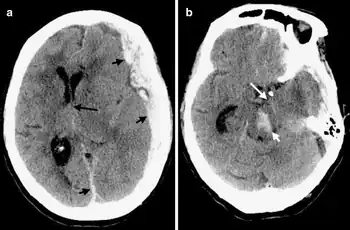

Duret haemorrhages are small linear areas of bleeding in the midbrain and upper pons of the brainstem. They are caused by a traumatic downward displacement of the brainstem.[1]

Duret haemorrhages can be demonstrated by medical imaging techniques of CT or MRI though difficult.[9]